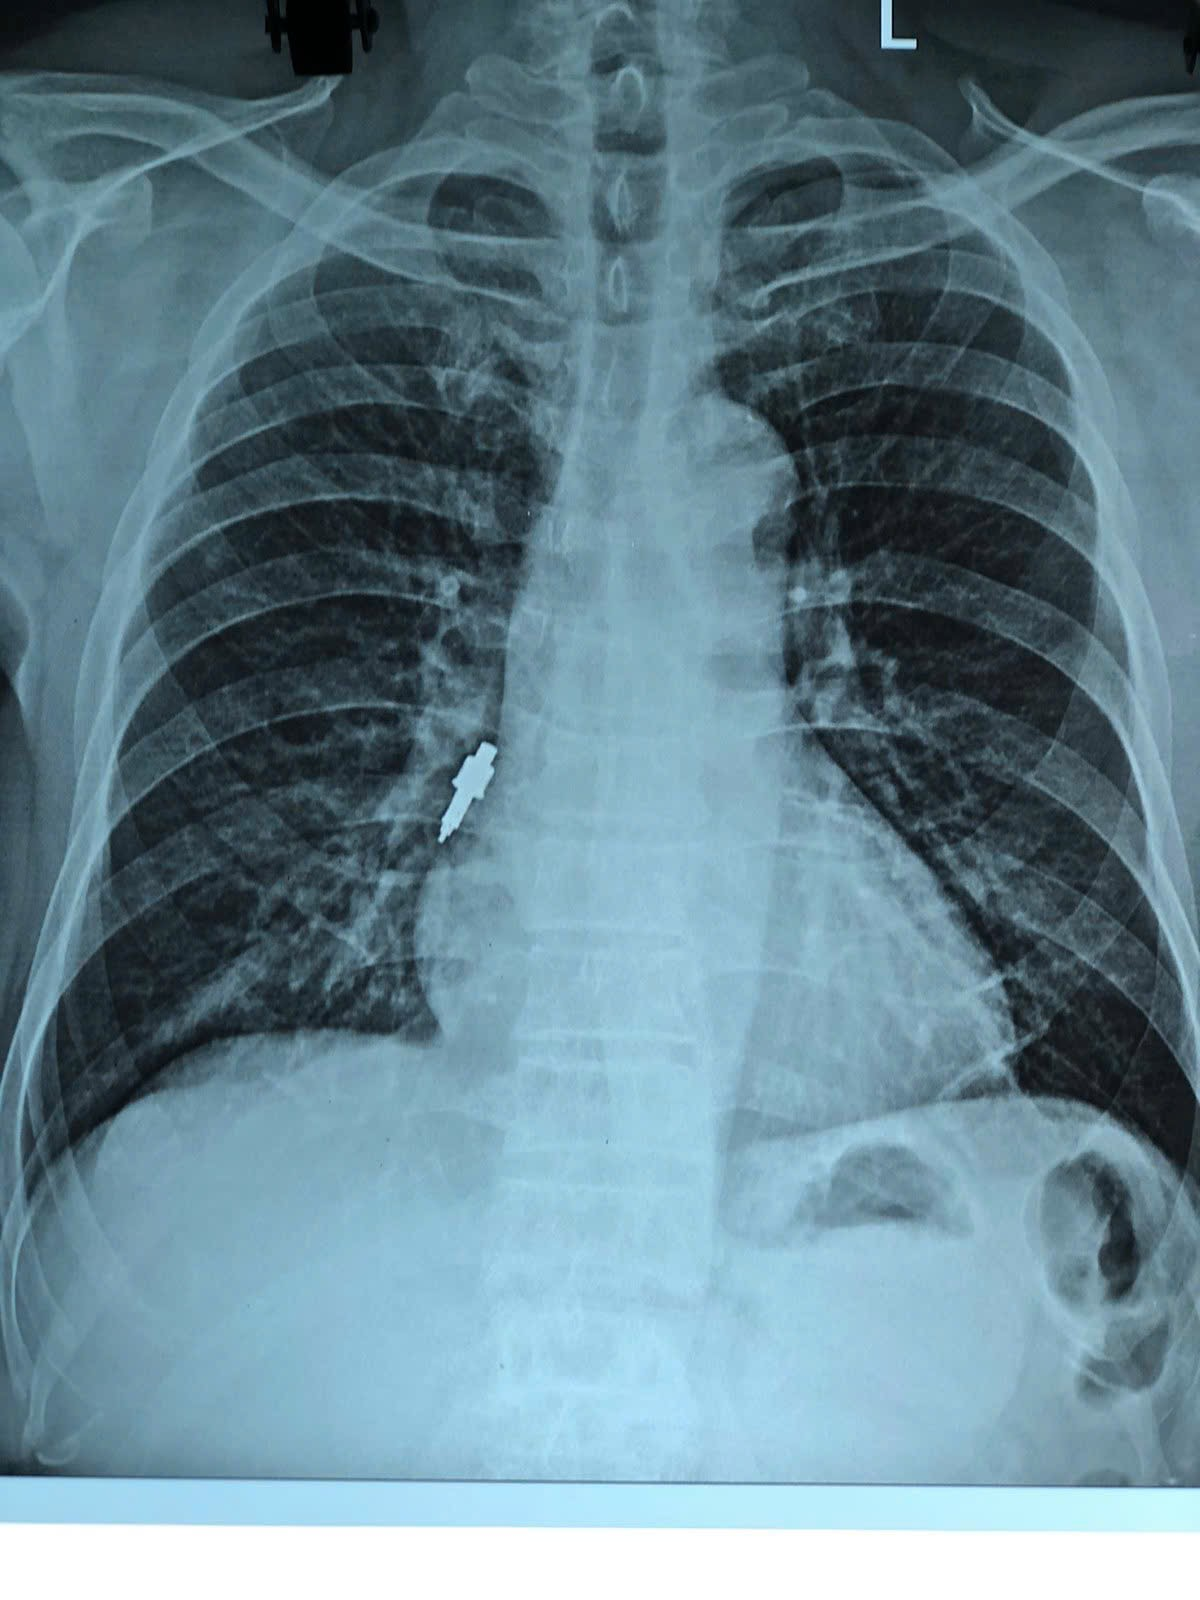

Trong quá trình thao tác, bác sĩ nha khoa thông báo có đánh mất một dụng cụ nhưng không xác định được vị trí. Sau đó, bệnh nhân xuất hiện ho nhẹ kéo dài. Đến hôm trước, cơn ho tăng dữ dội khiến gia đình phải đưa đi khám và chụp X-quang. Kết quả cho thấy một dị vật nằm gọn trong phế quản phải, và bệnh nhân được chuyển gấp đến Bệnh viện Hữu Nghị.

Tại bệnh viện, bệnh nhân được chỉ định nội soi phế quản cấp cứu. Quá trình lấy dị vật gặp nhiều thách thức lớn: dị vật bằng inox, trơn, kích thước "khủng" với đường kính chỗ to nhất lên đến 1 cm và dài 2,5 cm, lại mắc sâu và chặt vào phế quản phải. Loại dị vật này không thể gắp được bằng kìm sinh thiết thông thường.